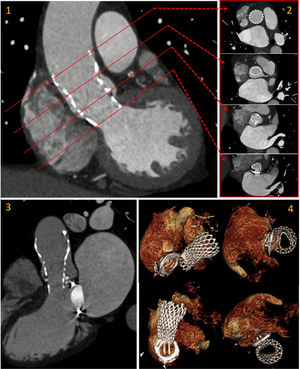

A post-procedural cardiac computed tomography to assess prosthesis morphology and the residual regurgitation mechanism was performed1 (Panel 1).

Transcatheter aortic valve replacement in MMV patients requires careful device selection and precise positioning due to the balance between avoiding MMV interference with low implantation and minimizing embolization risk from high positioning in mildly calcified valves.2 For this patient we considered this position the best possible result (Figure 1).

Post-procedural cardiac CT to access prosthesis morphology: modified coronal plane (1), short-axis (2), long-axis 3-chamber view (3) and volume rendering depicting the relation of TAVI prosthesis with the MMV with the restriction in expansion (elliptical shape) in the distal struts (4). This deformation is below the plane of the valve (CoraValve has a supraannular design).